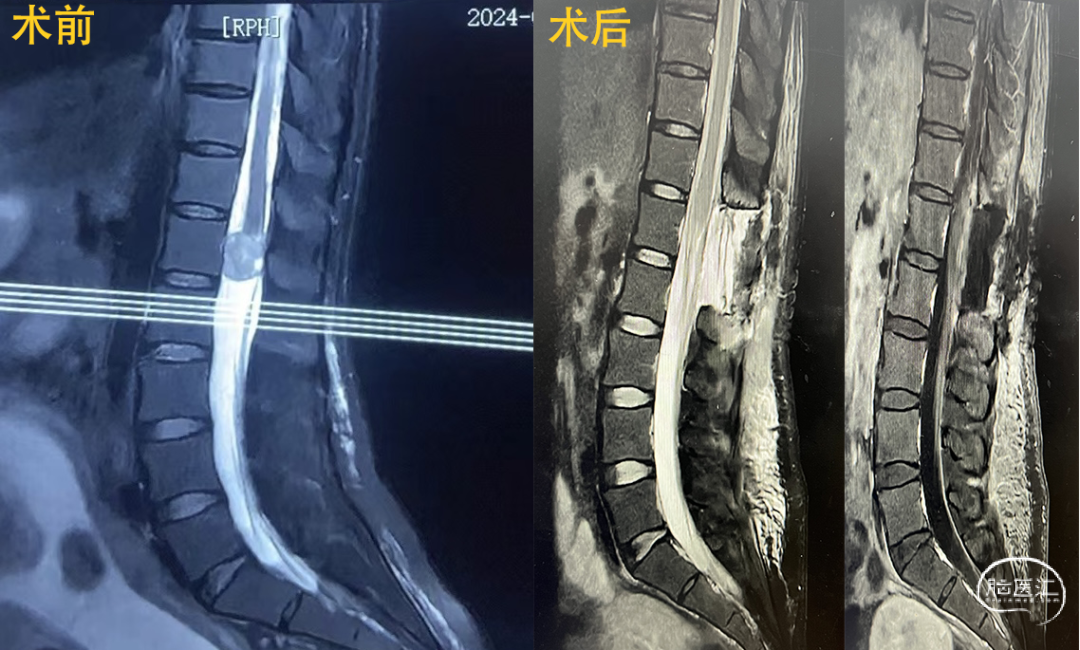

6.椎管肿瘤切除术